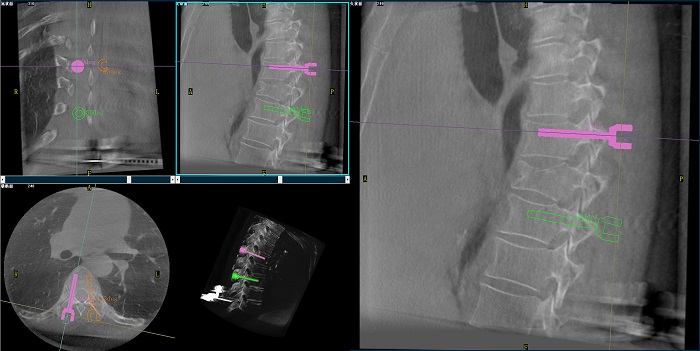

②機(jī)器人輔助胸椎手術(shù)操作難點(diǎn)之路徑規(guī)劃

人體胸椎的椎弓根較腰椎更狹窄,周圍有重要的神經(jīng)和血管,選擇合適尺寸和長(zhǎng)度的螺釘至關(guān)重要。螺釘過粗可能損傷椎弓根,過細(xì)容易發(fā)生形變,固定強(qiáng)度不夠;螺釘過長(zhǎng)可能穿透椎體前緣,造成損傷,過短則固定不牢。

普愛醫(yī)療手術(shù)導(dǎo)航定位系統(tǒng)解決方案

使用機(jī)器人輔助手術(shù),醫(yī)生不僅可以在影像的引導(dǎo)下,一次性完成多枚螺釘?shù)穆窂揭?guī)劃,提高手術(shù)效率,而且可以精確地選擇螺釘?shù)慕嵌?、直徑和長(zhǎng)度,提高手術(shù)的成功率。